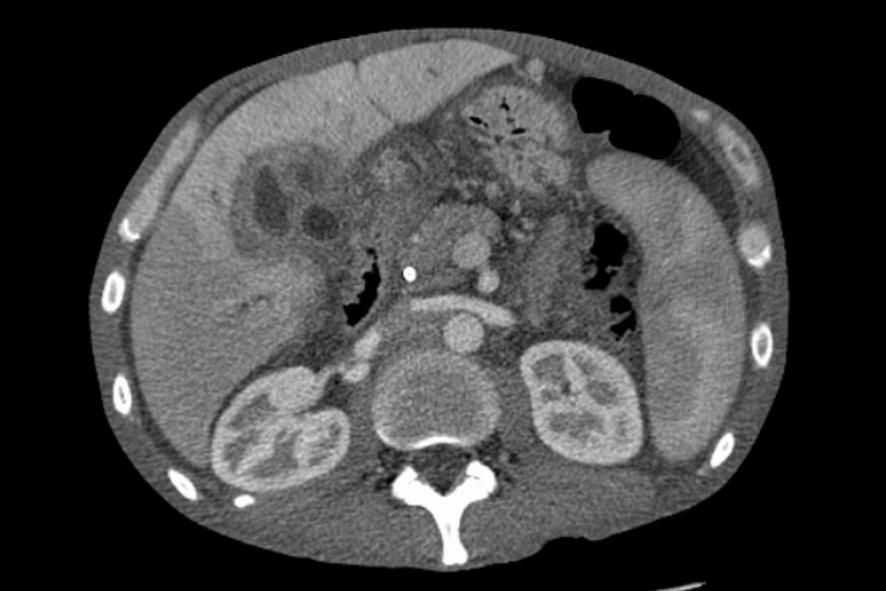

- 영상 검사: 초음파와 CT 그리고 MRI 등으로 간암의 존재와 크기, 위치를 파악합니다.